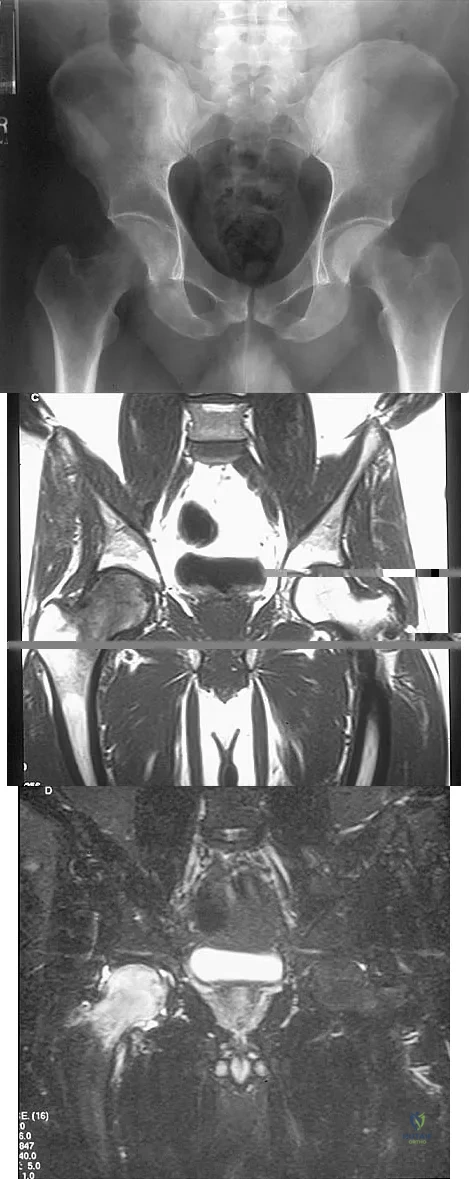

Figures 10a through 10c show the plain radiograph and MRI scans of a 41-year-old man who has right hip pain. What is the most likely diagnosis?

Explanation